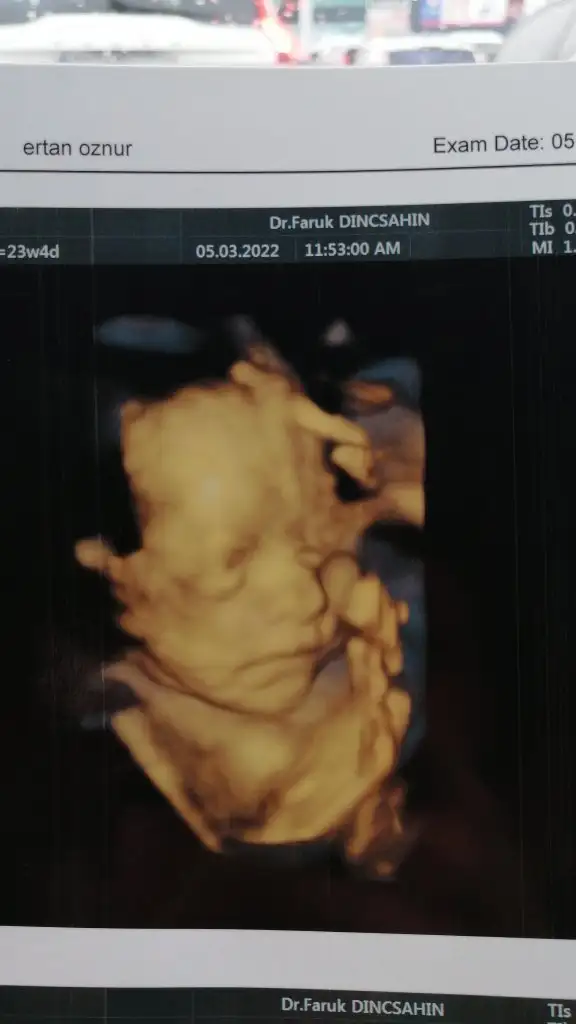

Bugün kontrele gittik. Çok şükür herşey yolunda. Rahim ağzı kapalı. Yeterli suları var. Ve gelişimleri gayet yerinde.

28 ve 29 cm. Geldiler. Kiloları da 603 gr ve 610 gram.

Bebeklerim den biri çok net gösterdi yüzünü. Renklide inanılmaz güzel göründü. Ama diğeri sürekli ellerini kapattı durdu. Görüntü alamadık.

Durum böyle. İşte bebişimin güzel fotosu